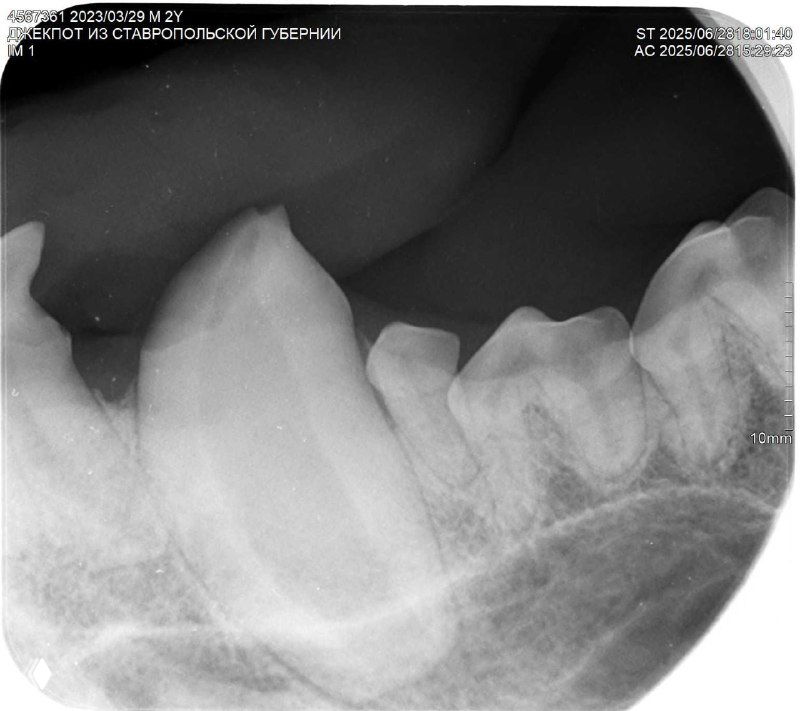

На снимках видно, какой ОГРОМНЫЙ корень у клыка - больше, чем видимая часть 😱